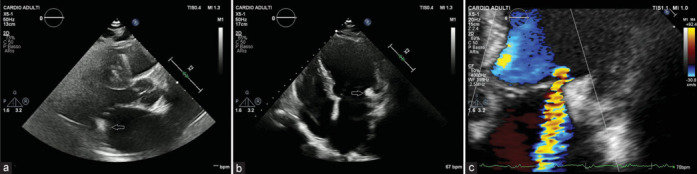

Caseous calcification of the mitral annulus (CCMA) is a rare variant of mitral annular calcification, and a multimodality approach is advised to ensure an accurate diagnosis. We report a case of a patient with CCMA, associated with severe mitral regurgitation. An 82-year-old woman was admitted due to worsening heart failure. Transthoracic echocardiography revealed a fixed, hyperechogenic mass, accompanied by restriction of the posterior mitral leaflet, and subsequent severe mitral regurgitation. Transesophageal echocardiography demonstrated a restricted motion of the posterior mitral leaflet, because of a large, echogenic mass (15 mm × 11 mm), attached to the mitral annulus, vacuolated with a central echolucent aspect, lacking acoustic shadowing. Contrast-enhanced cardiac computed tomography identified a distinct oval mass (18 mm × 11 mm × 19 mm) presenting a central hypodense content and peripheral calcification, strongly suggestive of CCMA. Considering the patient's profile, surgical valvular replacement was considered unsuitable. Therefore, a transcatheter edge-to-edge repair was performed, resulting in mild residual regurgitation.